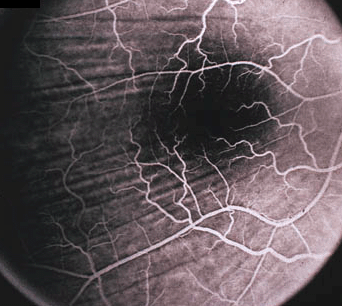

脉络膜视网膜皱褶(#2,2)

脉络膜视网膜皱褶(#2,1)